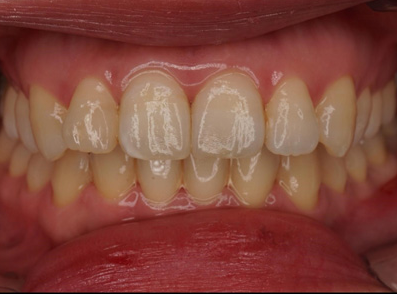

before

after

CASE 01

前歯の虫歯の治療

• 施術概要

虫歯の部分だけを最小限丁寧に取り除き、周りの歯の色になじむ自然な白い素材(レジン)で、元のきれいな形に整えます。これにより、口元の見た目をより自然な印象に近づけることを目指します。ダイレクトボンディングを実施。

• 金額

33,000円(税込)

• 期間・回数

小さい虫歯に関しては1回。 虫歯が神経まで到達している場合は、治療回数は2〜4回かかります。

• リスク・副作用

経年劣化によりレジンがすり減ったり着色し、将来的に再治療が必要となる場合があります。